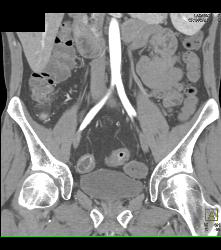

Increased Blood Flow to Mesenteric Vessels